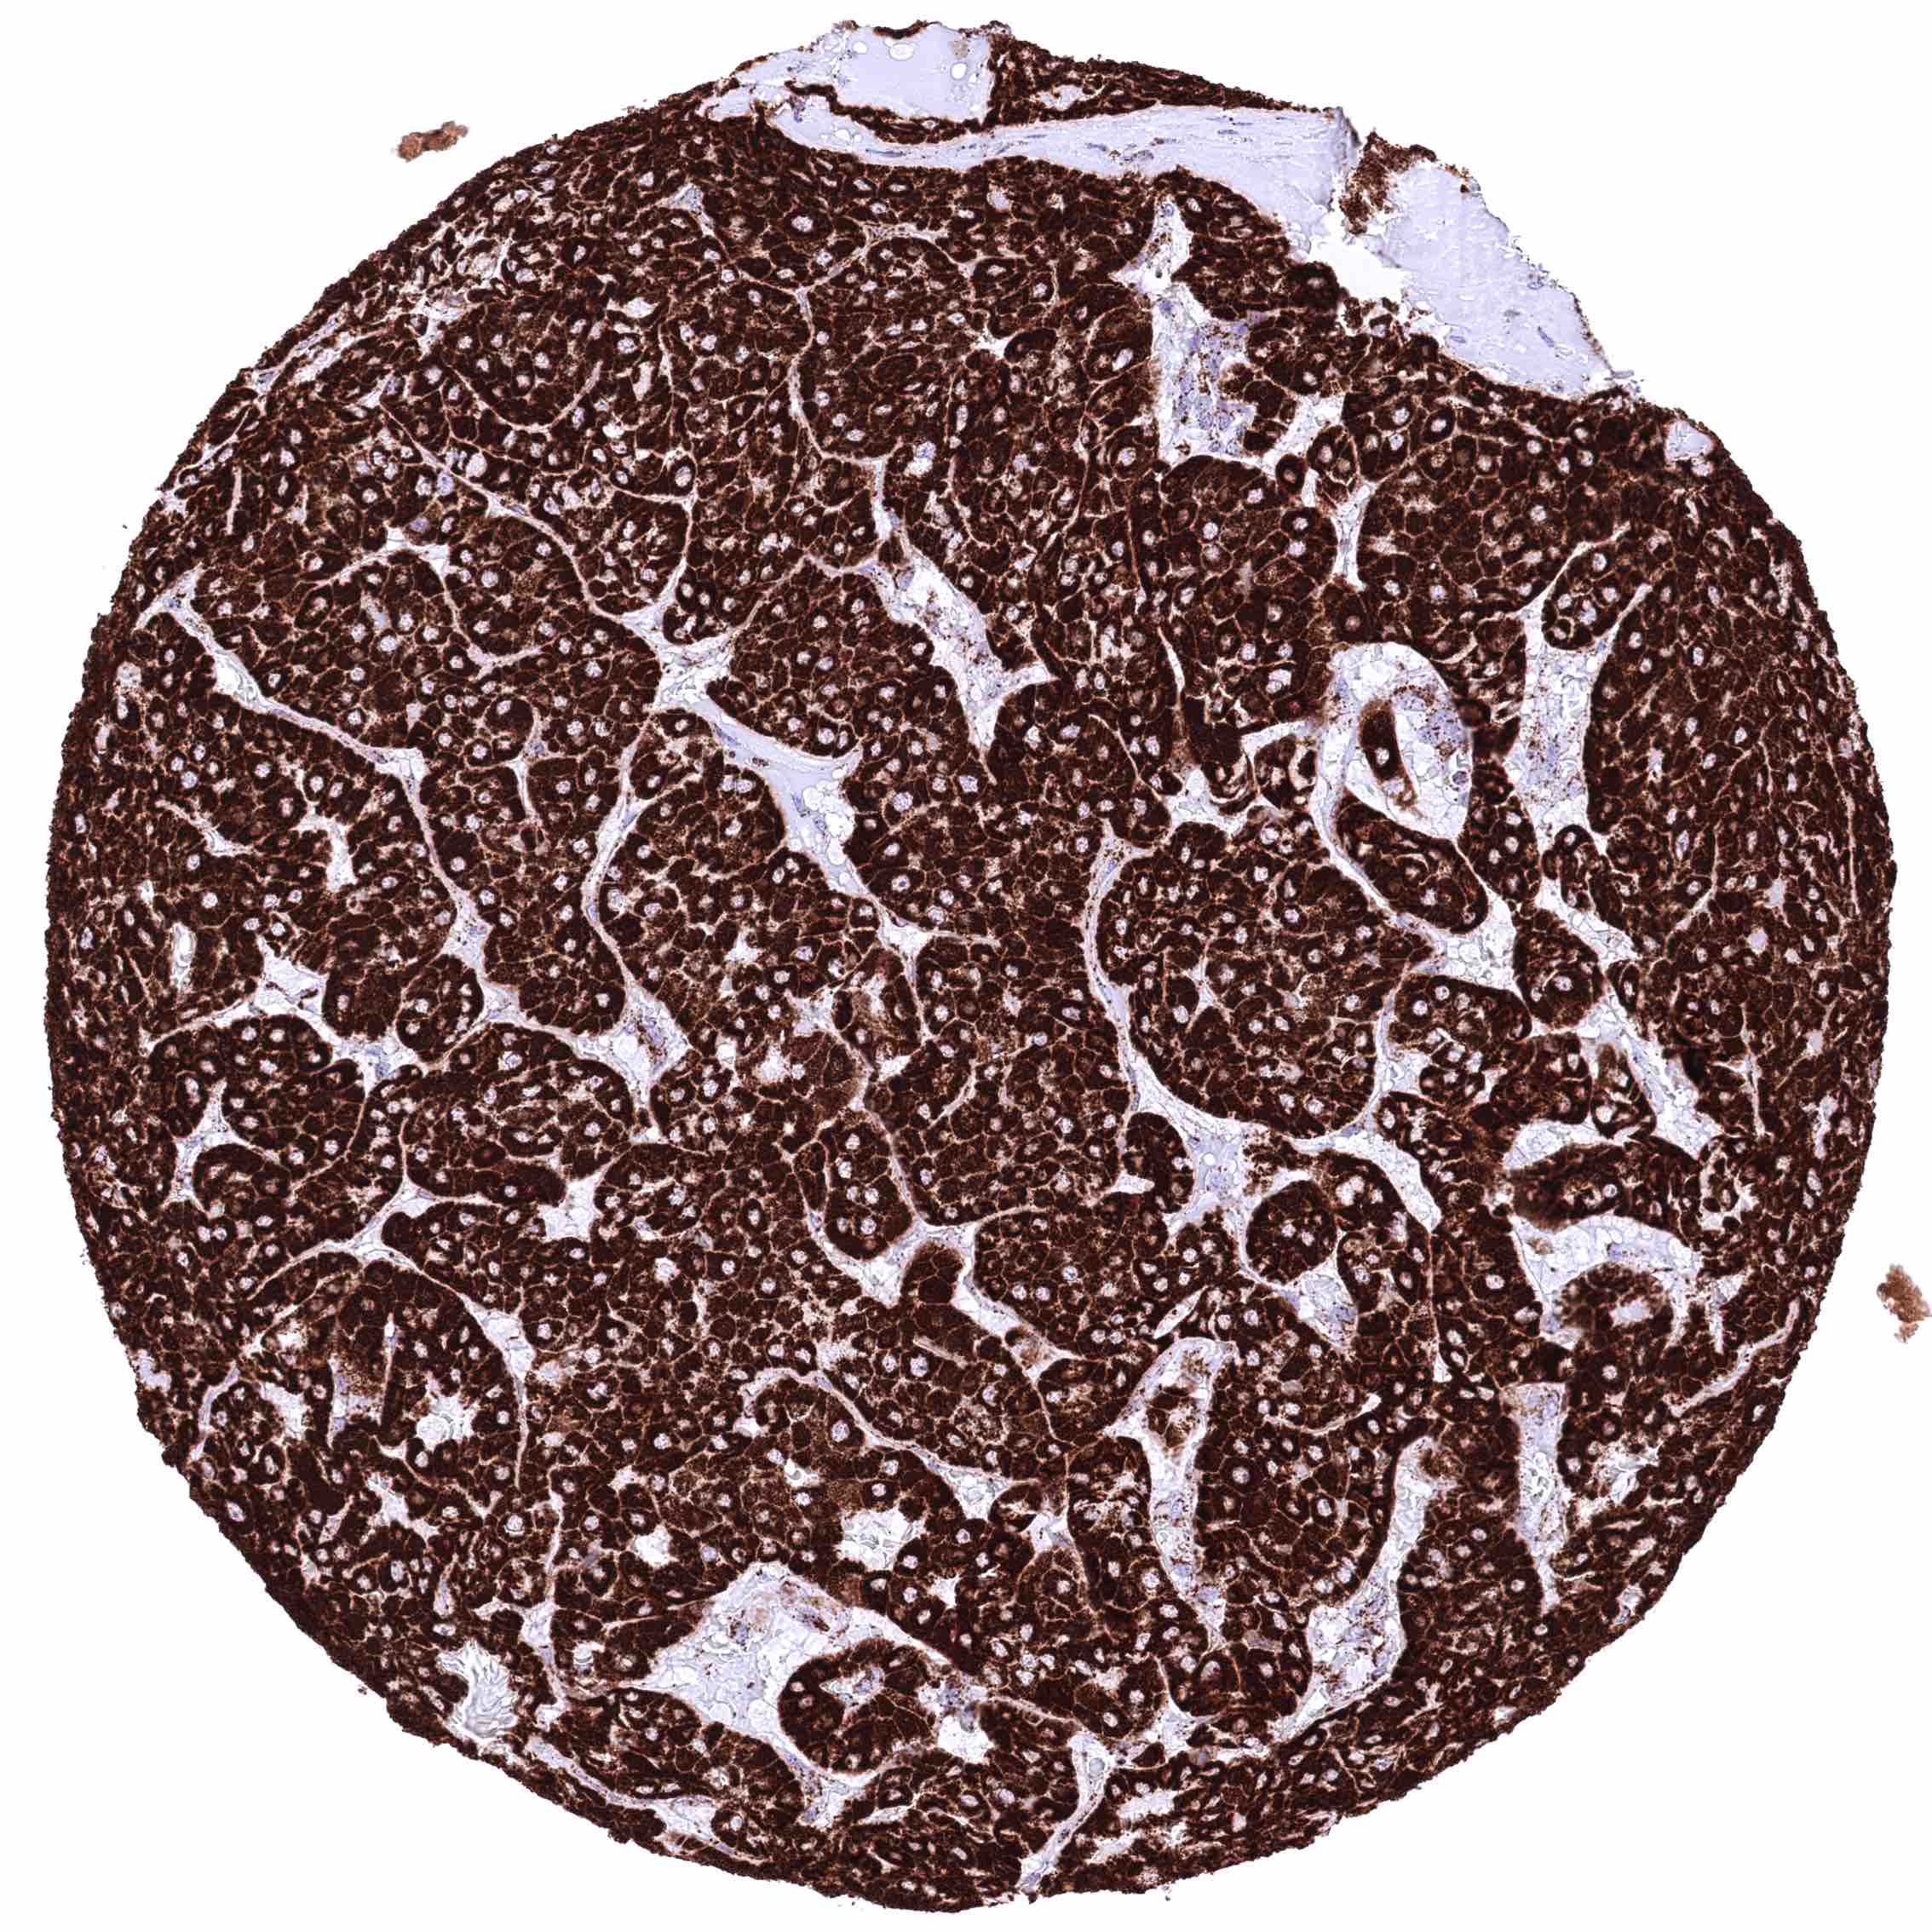

Salivary gland – Warthin tumor with intense ATP5J staining of tumor cells.